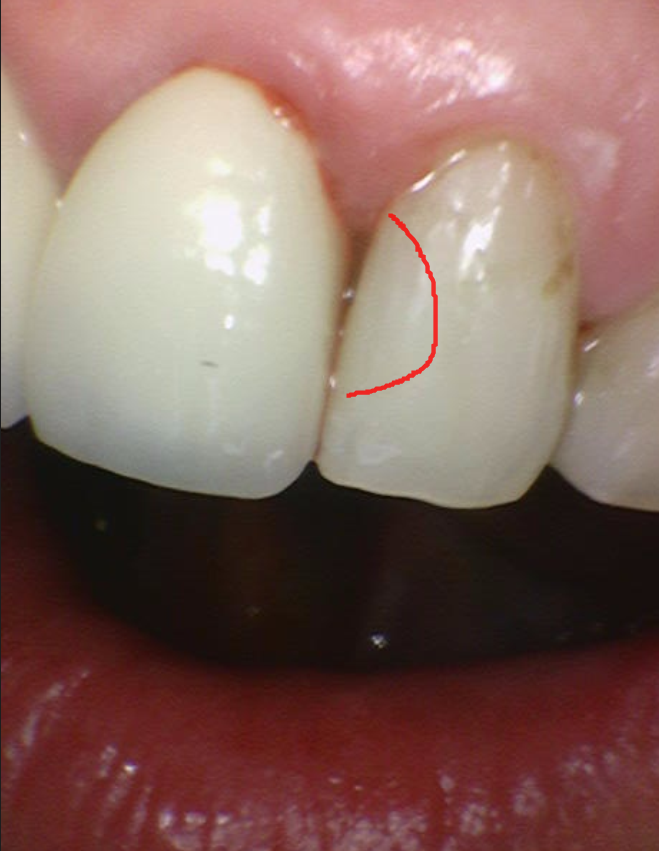

231127

조금만 손을 보았는데도 푹푹 들어가네요~~~

이것들을 깨끗하게 제거해주어야 재발도 없이

떼워줄 수 있습니다

충치 범위가 넓지는 않아

앞니 충치 레진으로 치료가 가능할 것으로 판단되었습니다.